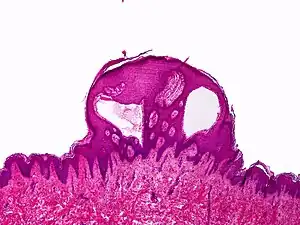

| Lymphangioma circumscriptum; only stratum papillare is affected. | |

A biopsy of the affected skin and histological examination under the microscope is necessary to diagnose lymphangioma circumscriptum.